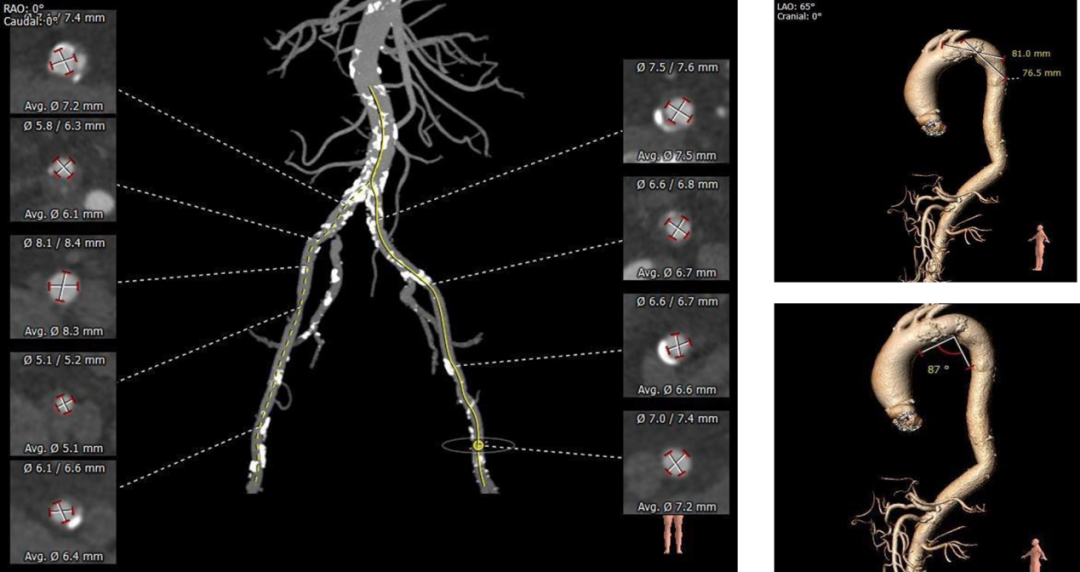

主动脉根部评估:

瓣环上解剖结构评估:

外周血管及主动脉弓解剖:

1.根据外周入路情况推荐左侧股动脉作为主入路,右侧为辅助入路。

2.根据当前影像资料,推荐跨瓣角度为RAO 14° CAU26°左右( 双窦展开位),预扩角度为RAO 14° CAU26°左右( 双窦展开位);推荐释放角度RAO 14° CAU26°左右( 双窦展开位)。

3.根据CT测量瓣环及瓣上结构数值,推荐选择22mm球囊预扩张,AV26瓣膜。